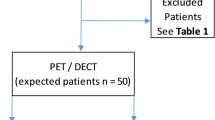

The primary endpoint of the pilot study was met in that it was feasible to deliver a PET-CT-based plan to ≥ 60% of patients (Fig. 1). The secondary endpoint of the pilot study was a comparison of GTV, PTV, and OAR DVHs between conventional 3-D plan and PET-CT-based 3D plans, and this was also achieved. It was feasible to analyse and to compare the differences in the DVCs to the OARs on the CT and PET-CT-based plans.

From August 2007 to February 2013, 49 eligible patients were enrolled. Three patients were found to be subsequently ineligible, 9 had disease progression, 1 patient died before they received RT, and 13 others did not receive RT for other reasons. Three patients died before the 3-month follow-up CT, 4 patients did not have their progression confirmed with a PET scan, and 4 others did not progress. Consequently, data from 12 patients were available for analysis of the primary endpoint. Figure 2 is a participant flow diagram that includes the numbers enrolled, received intended treatment, and analysed for the primary outcome.